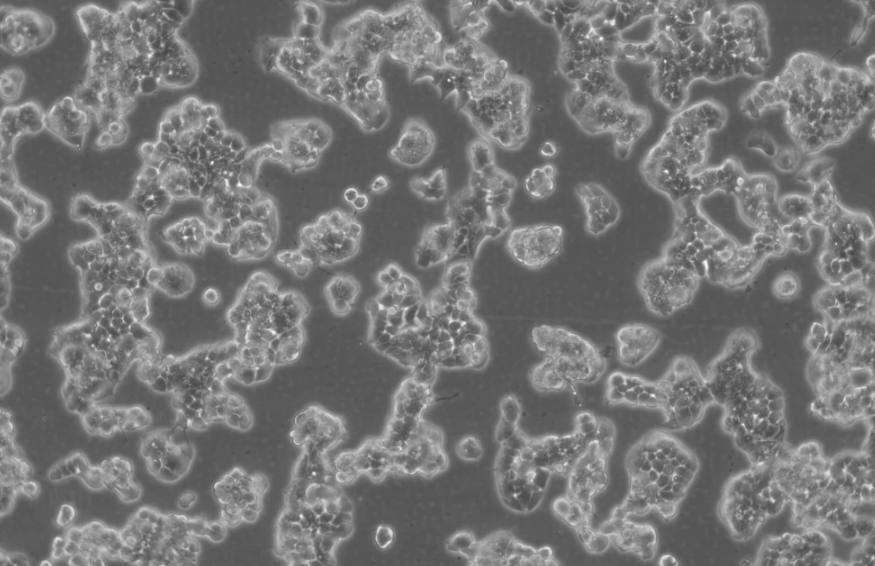

形態(tài) |

上皮細(xì)胞樣 |

生長(zhǎng)特征 |

貼壁生長(zhǎng) |